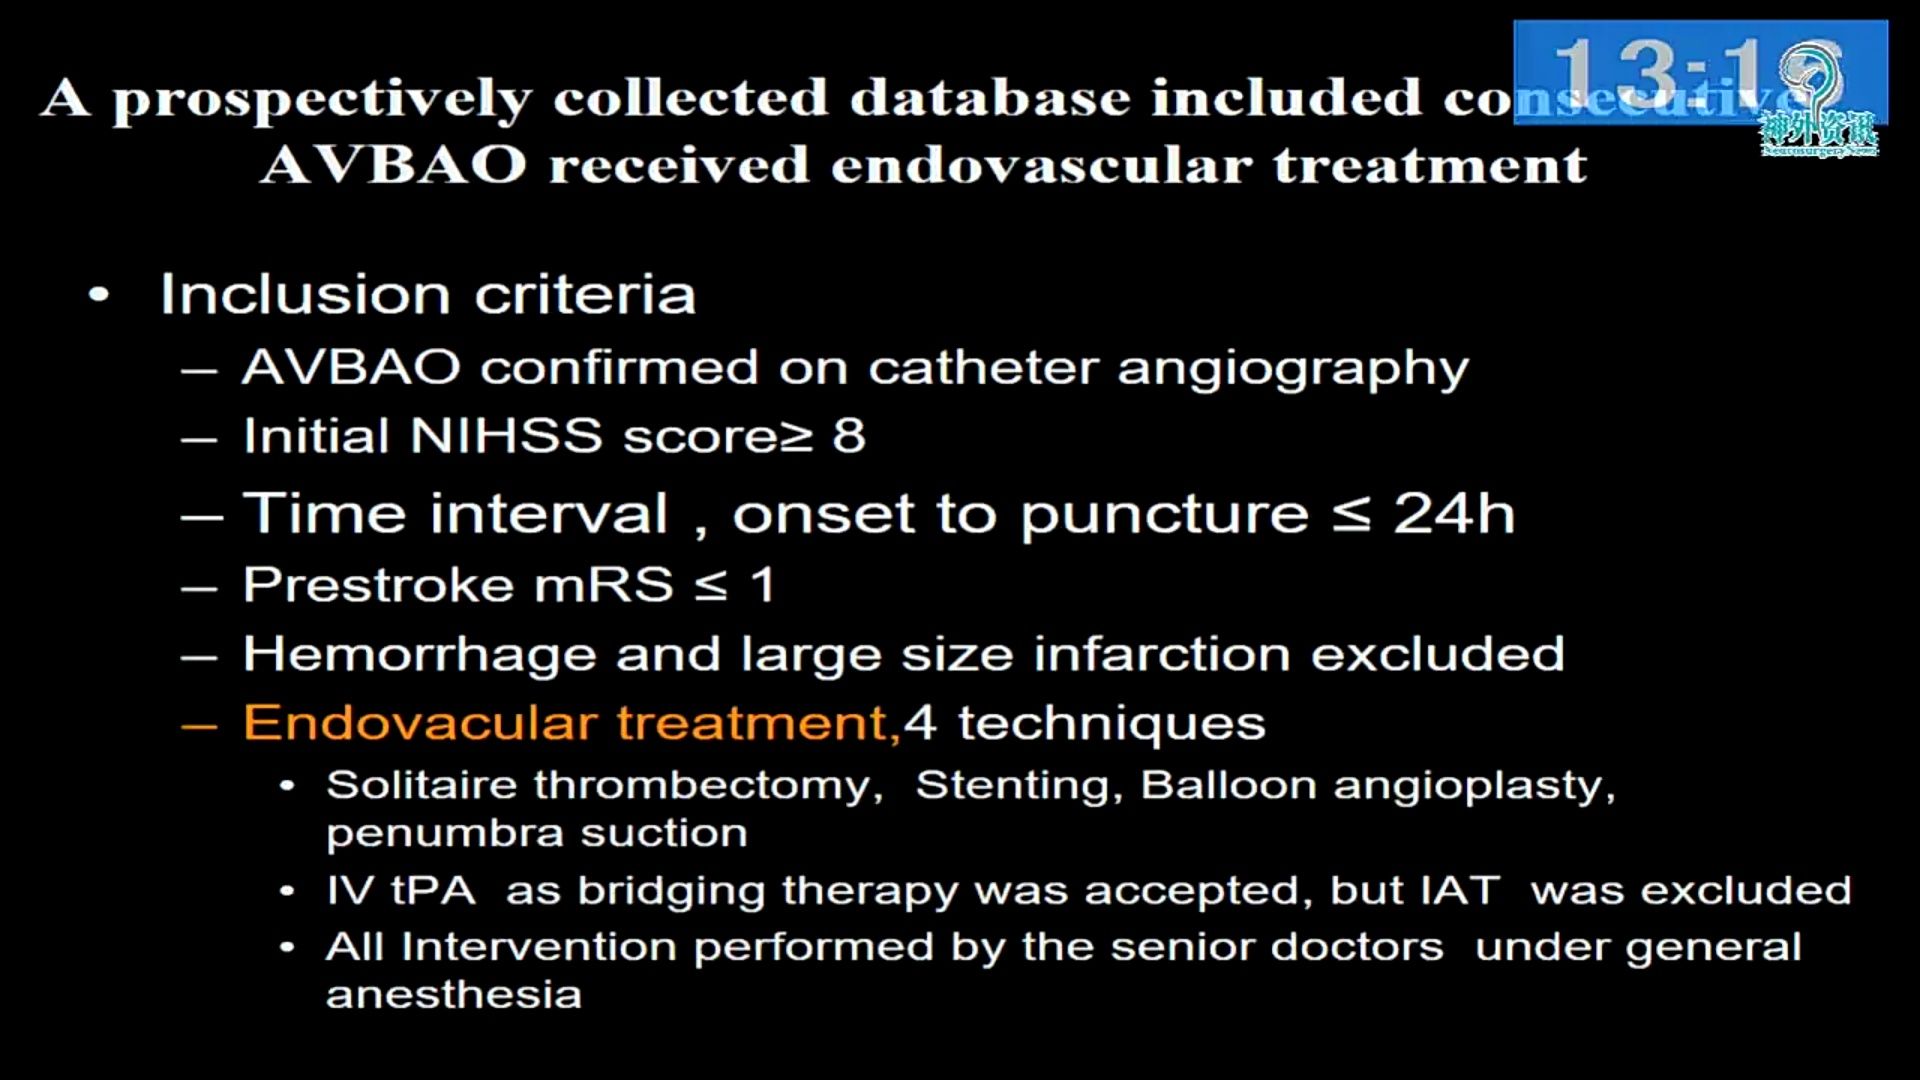

急性椎基底动脉闭塞血管内治疗